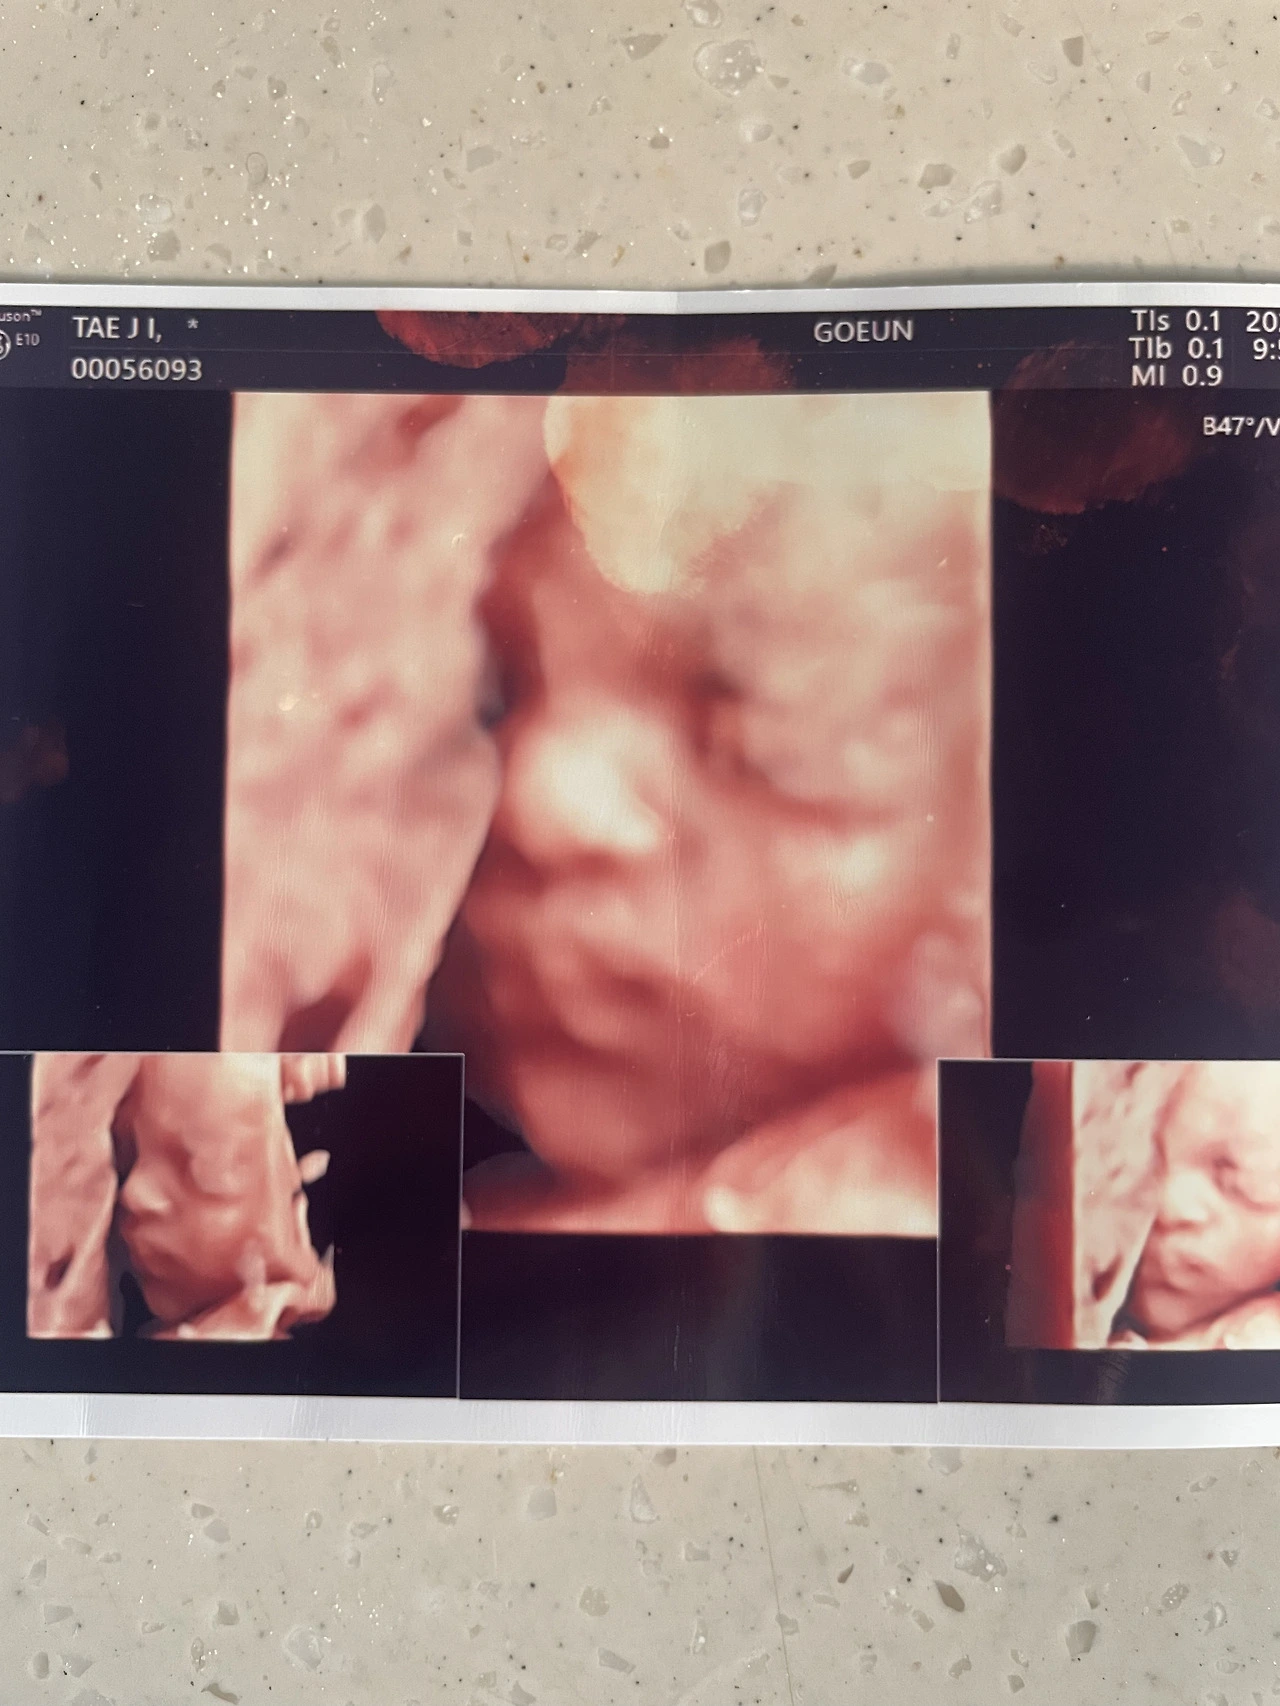

남매에게 입체초음파 사진을 꺼내 임신의 증거를 보여주자, 아들은 내게 조작사진이라며 믿으려 하지 않았다. 자신의 태아적 사진을 날짜를 바꾸어 조작한 것에 불과하다며 콧웃음을 쳤다.